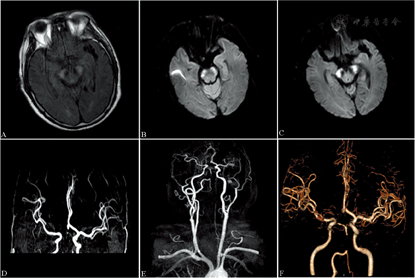

诊治过程:入院次日患者逐渐出现嗜睡,呼之可应,高级认知功能检查不能配合,查体欠配合,双侧瞳孔等大等圆,直径约3 mm,对光反射灵敏,双侧眼球各向活动不配合,可疑构音障碍,伸舌、示齿不合作,四肢肌张力正常,四肢可有自主活动,但不能配合肌力查体,四肢腱反射减弱,右侧病理征阳性。NIHSS评分13分。完善头颅MRI示双侧大脑脚及脑桥急性梗死灶(图1A,图1B,图1C)。头颈部磁共振血管造影(magnetic resonance angiography, MRA)和CT血管造影(CT angiography, CTA)示:(1)右侧大脑前动脉A1段未见确切显影,右侧大脑前动脉由前交通动脉供血;(2)双侧大脑后动脉闭塞;(3)右侧椎动脉优势型,基底动脉局部未见显影(图1D,图1E,图1F)。患者病情逐渐加重,转至神经科重症监护室,因颅内有新发梗死,考虑有症状颅内动脉粥样硬化性狭窄且病情进展,积极予以阿司匹林100 mg联合氯吡格雷75 mg抗血小板聚集、阿托伐他汀40 mg调脂稳斑等治疗。入院1周后患者病情仍进行性加重,逐渐出现言语不能、延髓麻痹、眼球活动受限、自右向左四肢瘫痪,NIHSS评分17分。住院治疗3周出院时神志清楚,NIHSS评分16分。院外继续康复理疗。8个月后随访时患者意识清楚,言语含混,可基本对答,四肢有自主活动,在搀扶下可行走,NIHSS评分5分,改良Rankin量表评分4分。

液体衰减反转恢复序列(A)和弥散加权成像(B~C)示双侧大脑脚及脑桥急性梗死灶。磁共振血管造影(D~E)和CT血管造影(F)示:(1)右侧大脑前动脉A1段未见确切显影,右侧大脑前动脉由前交通动脉供血;(2)双侧大脑后动脉闭塞;(3)右侧椎动脉优势型,基底动脉局部未见显影

BCPI的确诊有赖于及时完整的头颅影像学检查。典型的BCPI在弥散加权成像(diffusion-weighted imaging, DWI)中双侧大脑脚呈高信号,犹如迪士尼动画片中米老鼠的2只耳朵,故Asakawa等[1]称之为"米老鼠耳征"(Mickey Mouse ears' sign)。也有中国学者将此病灶比同于中国汉字"八"[4]。本组2例BCPI患者的DWI图像也非常符合此征(图1C和图2C)。Asakawa等[1]对9例经头颅CT或MRI确诊的BCPI患者进行的统计显示,病变除双侧大脑脚外,多累及脑桥。陈文伙等[2]报道的14例BCPI患者也多累及脑桥、小脑、枕叶等后循环供血区域。Chen等[3]报道的11例BCPI患者多累及枕叶、小脑及丘脑等。本组病例1梗死灶相对局限,仅累及脑桥;病例2梗死灶相对广泛,累及脑桥、延髓、小脑及枕叶等多个区域。但是,这2例患者的影像学都提示椎基底动脉系统存在狭窄或闭塞。